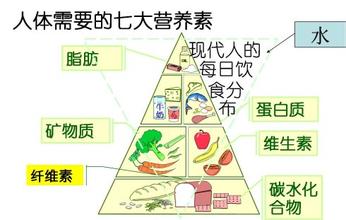

保证均衡饮食的原则是什么

保证均衡饮食的原则是什么 -

营养素的定义

营养素的定义 -

营养与优生有何关系

营养与优生有何关系 -